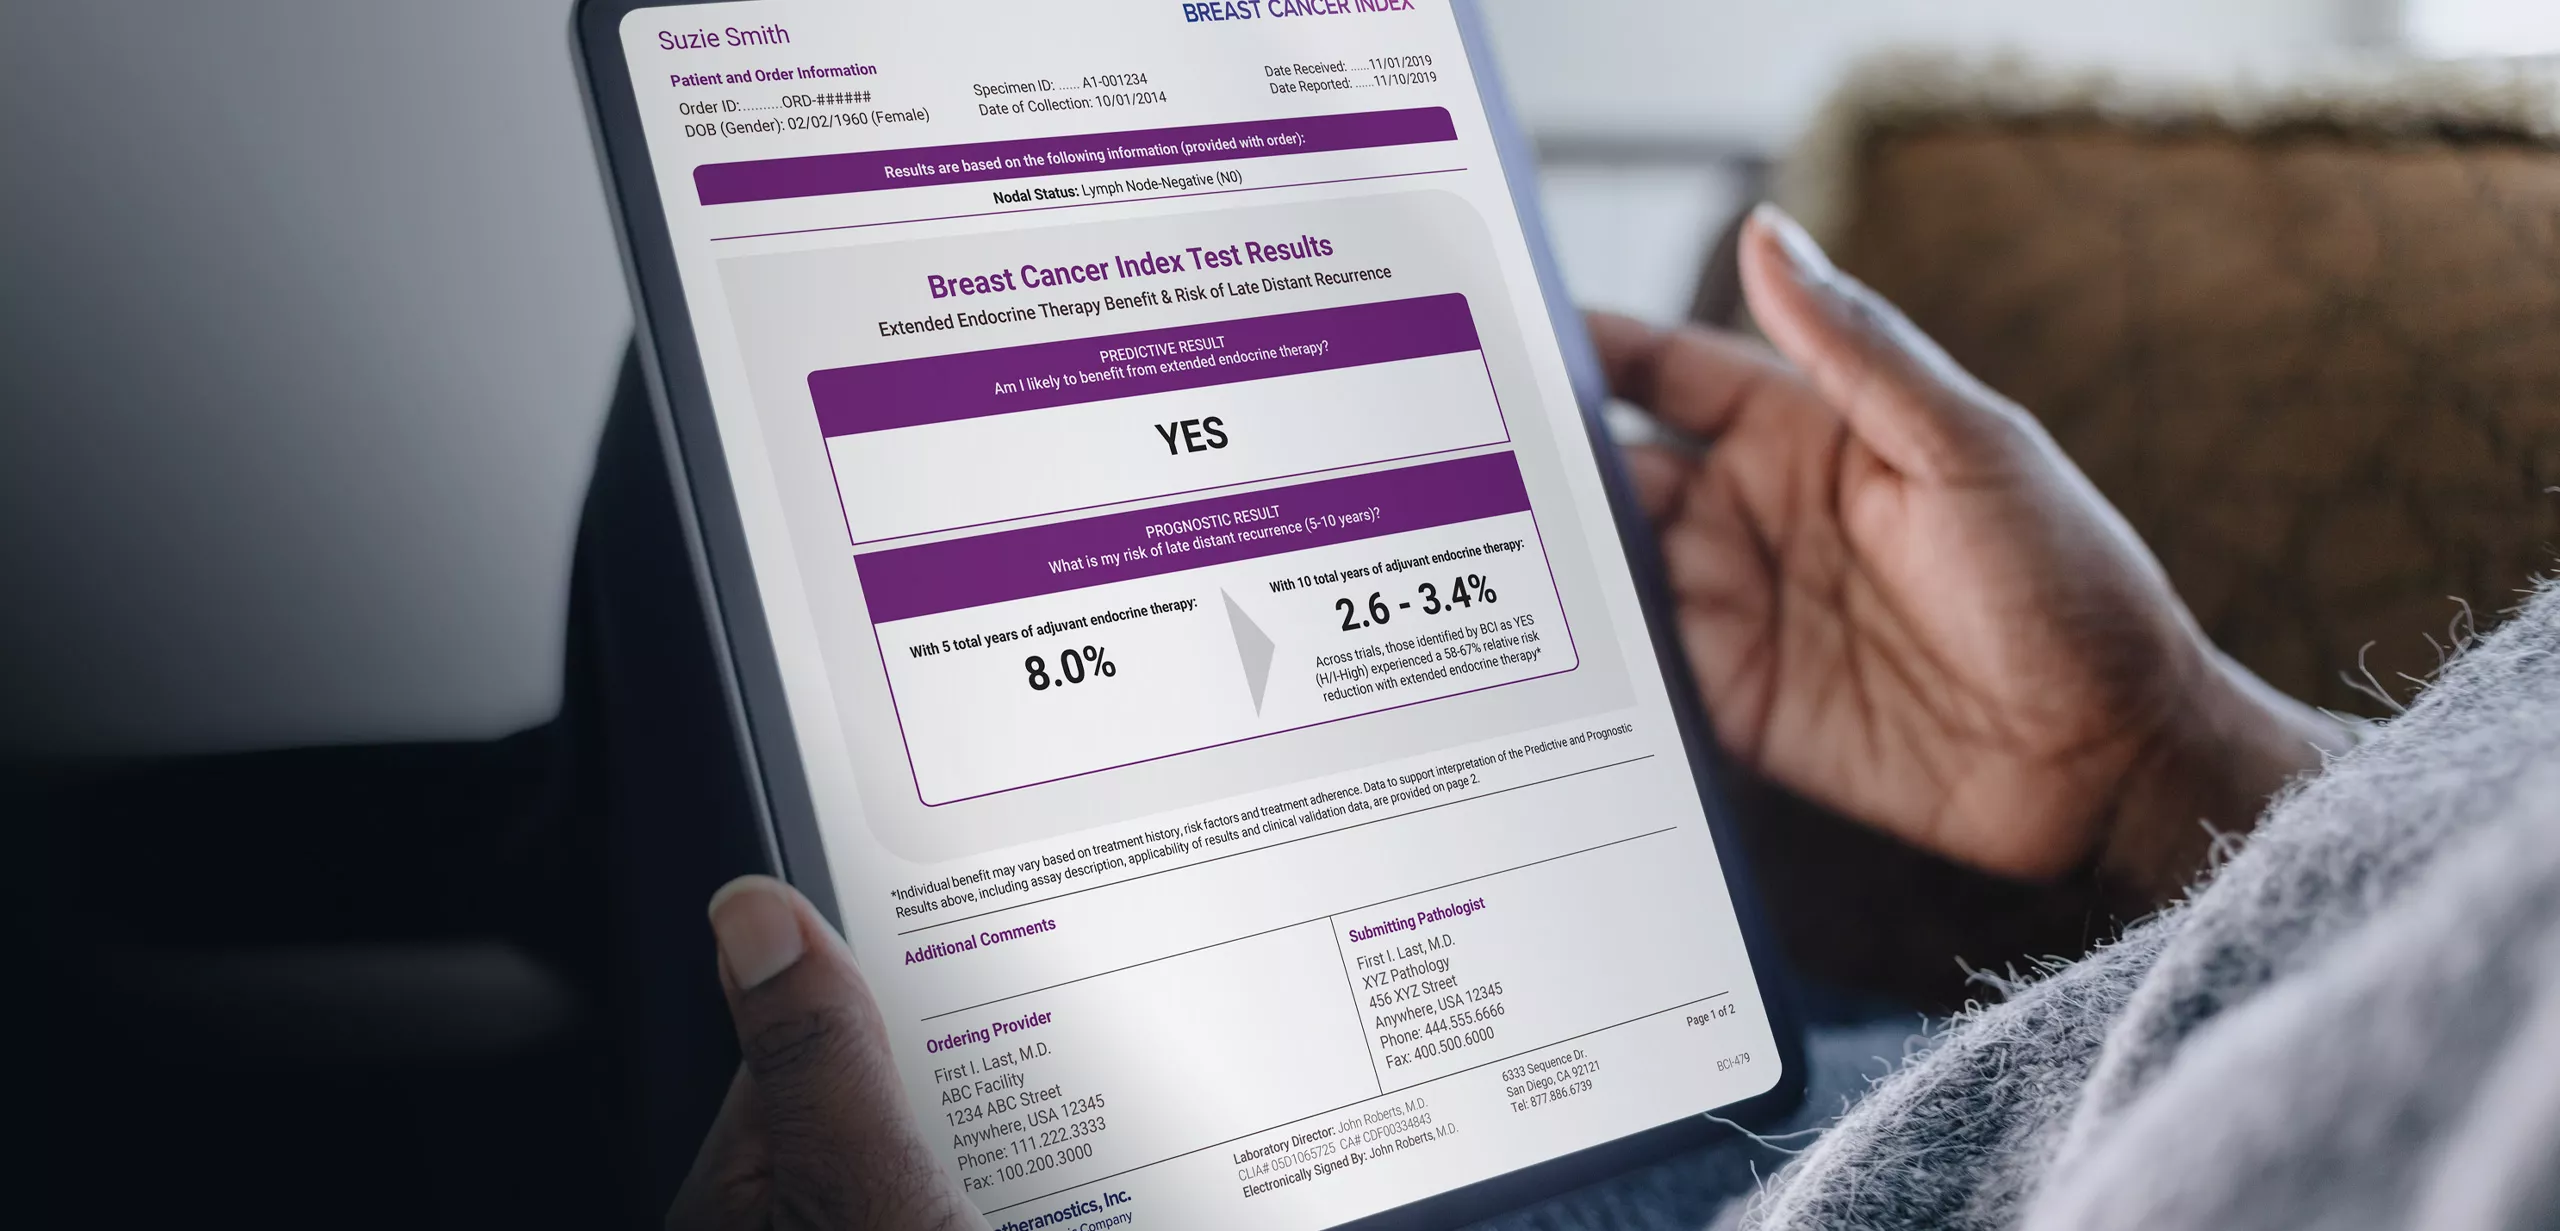

Beyond Screening: Breast Cancer Index® Test

As breast cancer survivors continue to get regular screenings throughout survivorship, understanding long term treatment plans is also essential. The Breast Cancer Index® test helps determine if a patient with HR+, early-stage breast cancer is likely to benefit from extending endocrine therapy to 10 years, or if she can stop at the 5-year mark and avoid potential side effects.